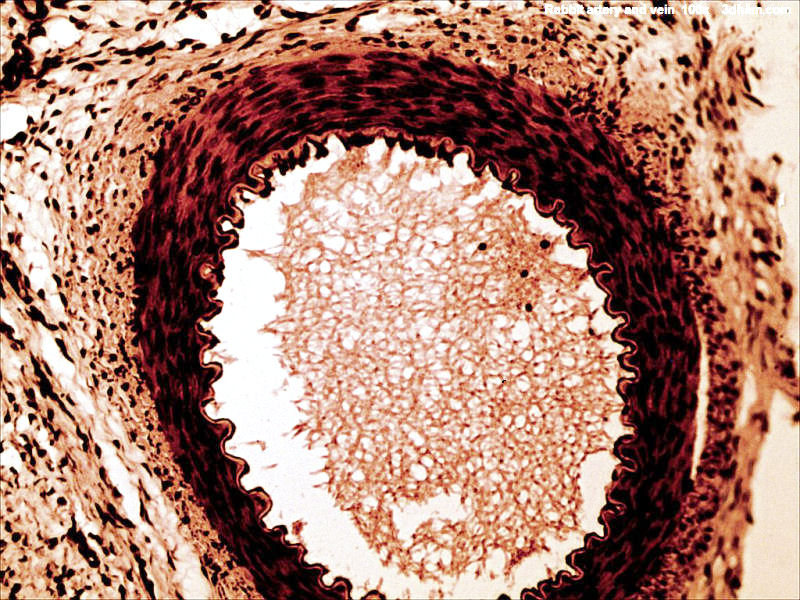

back rabbit artery and vein